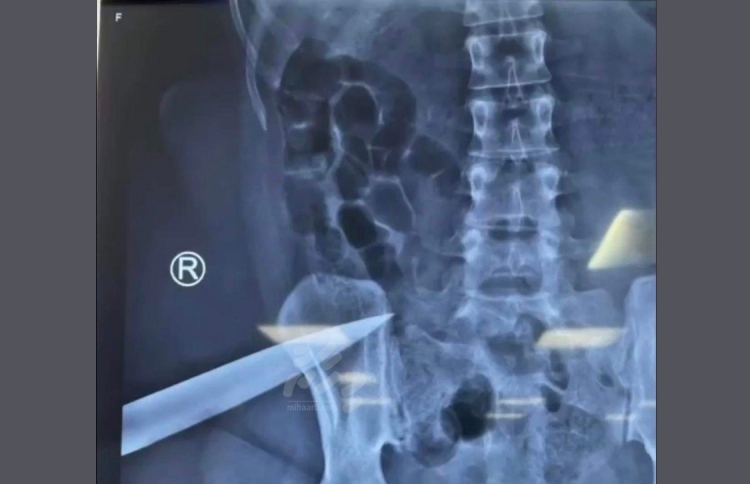

80 ބްލެޓް ދިރުވާލި މީހަކު 12 އަހަރަށް ޖަލަށް